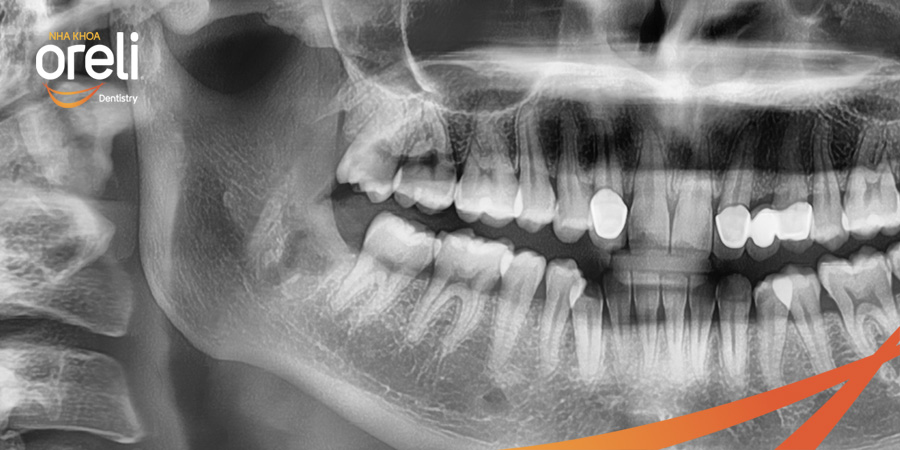

Nhổ răng khôn hàm dưới khó do mọc ngang – Case tại Oreli

Nhổ răng khôn

Mọc lệch